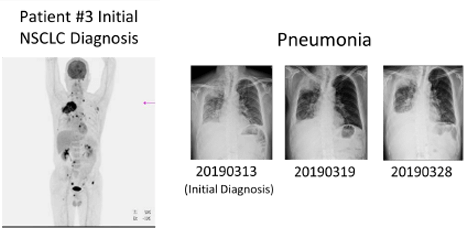

User Story #2

Patients with Lung Cancer Due to Exon 19 mutation in EGFR

- Exon 19 deletion was detected from patient’s tissue using qPCR

- Deletion was confirmed using patients’ blood sample using MoDEL™